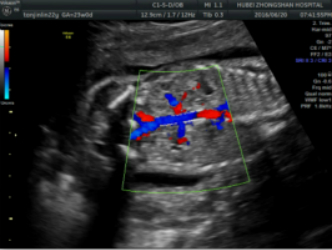

4.分娩前超声检查:超声重点观察指标包括:胎方位、胎儿大小、胎盘及胎儿循环、羊水量、胎盘成熟度、有无胎盘早剥或前置胎盘、脐带有无绕颈、脱垂等。这些指标对临产时医师选择正确的分娩方式,对母亲及胎儿健康平安至关重要。尤其对在整个孕期从未接受超声检查的准妈妈,为了母子的平安,分娩前务必接受一次超声检查。